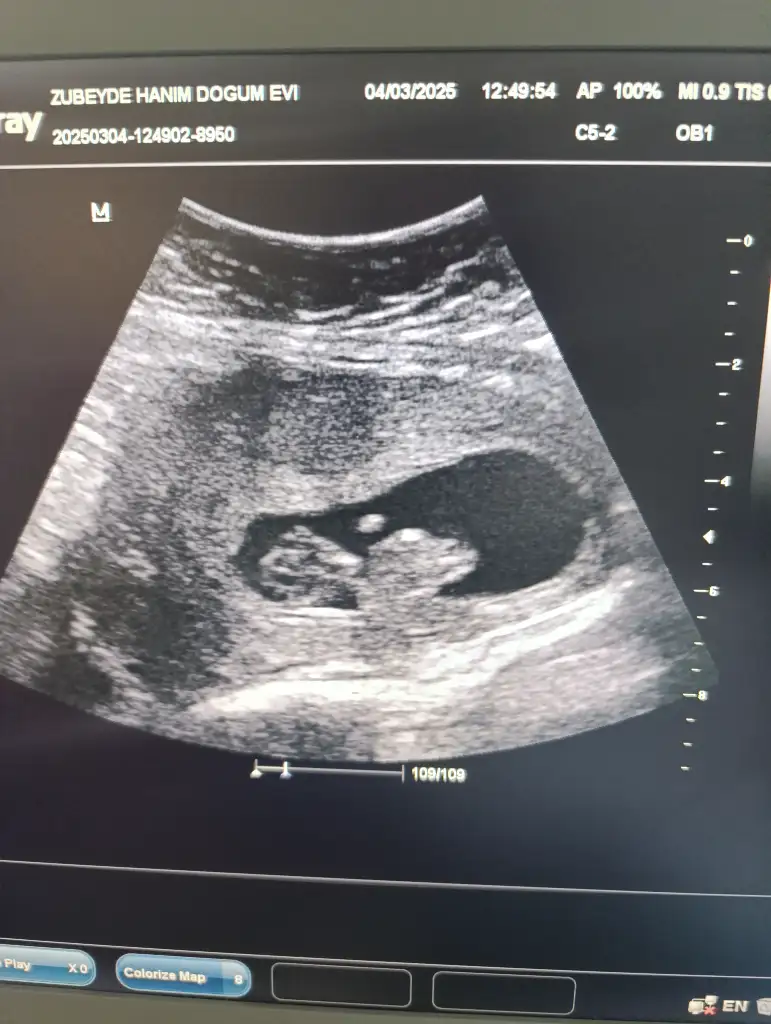

Bunada bakar mısınız rica edersemkız gibi

Bunada bakar mısınız

kızKızlar bana da bakar mısınız?? 13 haftalık

çok küçük ama kese kız gibiBana da yorum yapar mısınız 8 haftalık vajinal bakıldı